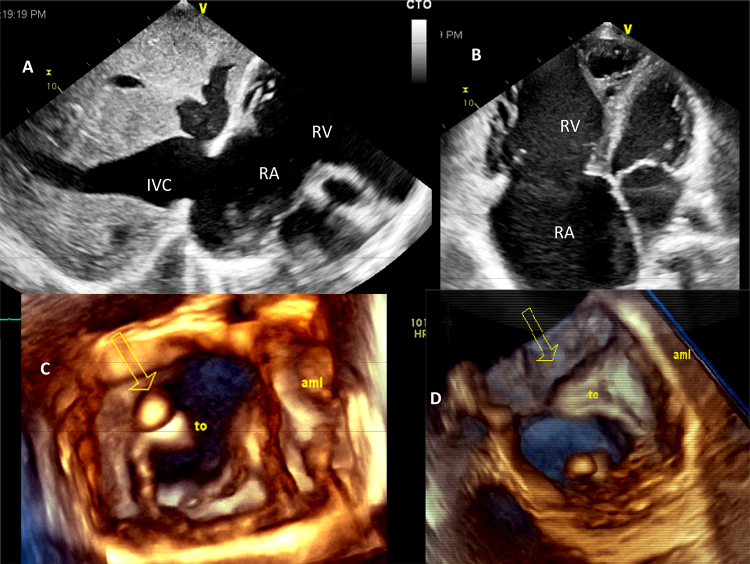

Fig. 2.

(A) Dilated inferior vena cava, hepatic veins and unguarded tricuspid orifice in subcostal view. (B) Rudimentary anterior and septal leaflets during systole with markedly dilated right atrium and the right ventricle in apical 4-chamber view. (C) 3D-echocardiographic image in diastole with a nodule attached to rudimentary posterior leaflet. (D, seen from the right atrium) Unguarded tricuspid orifice during systole with rudimentary anterior leaflet.

Two-dimensional echocardiography showed small left atrium and the left ventricle, markedly dilated right heart chambers, paradoxical ventricular septal motion, interatrial septum curved to the left, dilated inferior vena cava and hepatic veins, enlarged tricuspid annulus (48 mm), rudimentary septal and anterior tricuspid leaflet with a nodular mass attached to the vestigial anterior leaflet (Fig. 2). Septal leaflet of the TV was rudimentary but normally inserted. Posterior tricuspid leaflet and the papillary muscles were not visible. The right ventricular outflow tract was dilated with normal pulmonary arteries. Doppler interrogation of the right ventricular inflow and outflow showed low-velocity to-and-fro flow with a peak velocity of <1 m/s (Fig. 3).